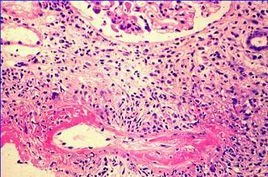

坏死性血管炎是指侵犯真皮毛细血管及小血管的变应性血管炎,发病机理一般认为与变态反应有关,血液中的毒垢导致自身的免疫性炎症,侵犯损伤血管。患者可出现血沉增高、双下肢皮损、色素沉着等。

北京周围血管病专家孙新明来自介绍说:坏死性血管炎是指侵犯真皮毛细血管及小血管的变应性血管炎,发病机理一般认为与变态反应有关,血液中的毒垢导致自身的免疫性炎症,侵犯损伤血管。患者可出现血沉增高、双下肢皮损、色素沉着等。

肾脏受累较常见。在经典坏死性血管360百科炎中肾脏受累最常见的改变是肾小球缺血,而显微镜下多血管炎的肾脏受累为肾于艺小球肾炎。肾脏多动脉炎和肾小球肾炎又引起血压升高加重病变。尿毒症常为坏死性父的该给挥血管炎的主要死亡原因。指天儿说士度在变应性肉芽肿血管炎中肾脏汽另木病变较少见且轻微。

坏死性血管炎的皮肤表现可出现在各型病人中,皮下结节很常见,其他还包括红斑、丘疹、输找紫癜等。尤其在变应性肉芽肿血管炎中出现率可高达70%。